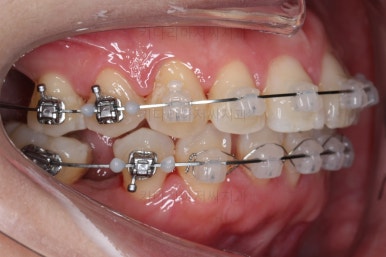

브라켓을 부착합니다.

이번 환자분이 선택하신 장치는 데이몬 클리어라고 하는 자가결찰 세라믹 장치인데요.

일반적으로 흔히 아시는 클리피씨 장치에 비해서 철사를 잡아주는 뚜껑까지 세라믹으로 되어 있어서 아마도 현존하는 세라믹 장치 중에서는 가장 심미적인 장치라고 볼 수 있습니다.

대신, 세라믹으로 되어 있다보니 강도 때문에 부피는 조금 더 커진다는 단점은 있긴 합니다.

장치 부착 직후의 웃는 모습과 입이 좀 더 나오는 양상을 참고해 주시고요.

참고로 입이 나오는 정도는 사람마다 매우 달라서 데이몬 클리어는 이정도 나온다는 기준은 딱히 없긴 합니다.